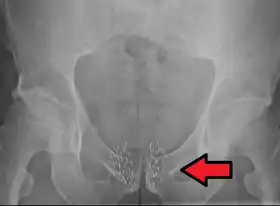

![]() Arrow points to brachytherapy beads used to treat prostate cancer. | |